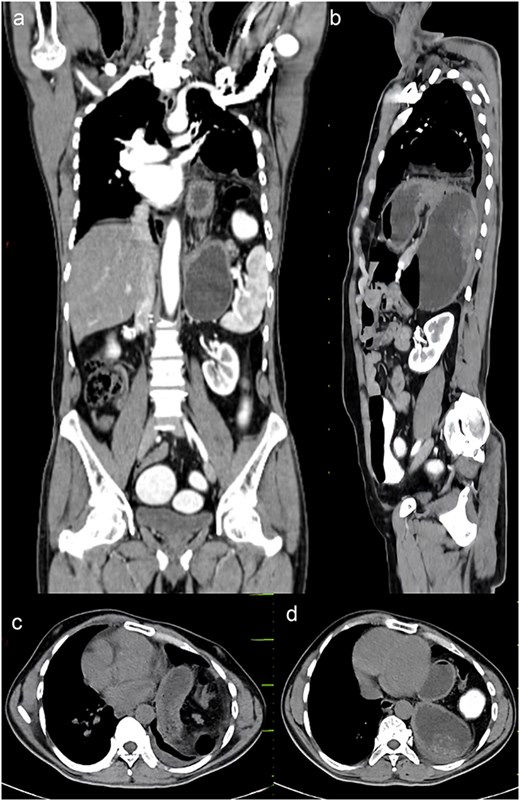

A chest x-ray was done, and it showed continuous internal air columns with abdominal gases, with a shifting of cardiac shadow to the contralateral side (Fig. 1). After stabilization of the patient, CECT thorax, abdomen, and pelvis was done which suggests left-sided diaphragmatic hernia with a defect of 28 mm with herniation of splenic flexure, entire left hemithorax. Obstructed loop seen within the herniated content with collapsed exiting loop s/o obstructed diaphragmatic hernia which led to mediastinal shift to right side and collapse of left lung (Fig. 2).

CECT abdomen and pelvis. (a) Sagittal view, (b) coronal view, (c, d) axial view.